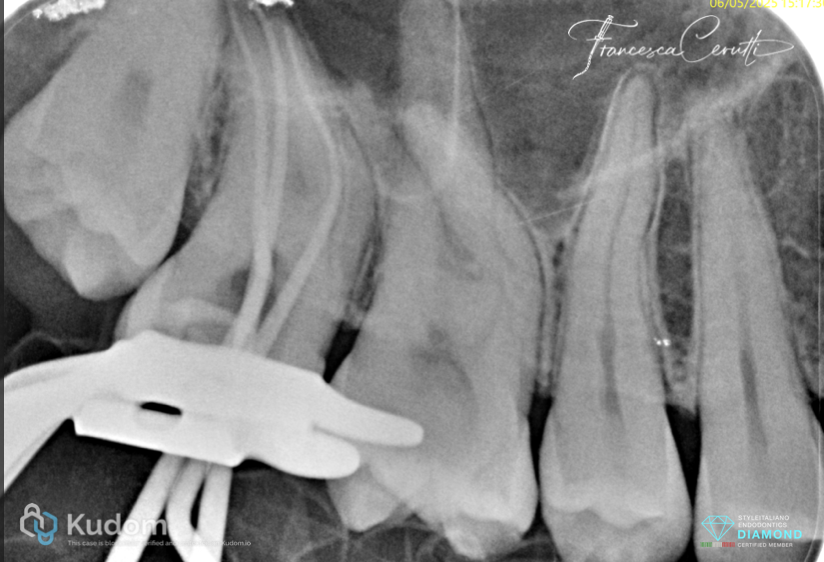

Fig. 6

Then I used the R1 file (13/.03) short to the estimated working length

Fig. 7

After that, I kept pre-flaring the root canals using the R2 (25/.04)